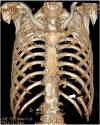

Displaced rib fractures can injure intercostal vessels leading to chest wall hematomas. As the bleeding occurs within the vessel, compression of the vessel wall helps in preventing further bleeding. Therefore, chest wall hematomas rarely result in shock. A thin 78-year-old man transferred to the emergency department with complaints of left dorsal pain due to an injury. He had a history of hypertension and aorta dissection. He arrived at the ED in a state of shock and presented with a large left dorsal wall mass. Subsequent imaging using computed tomography angiography revealed a large hyperdense hematoma at the left dorsal-flank wall along with rib fracture (11th intercostal artery). Moreover, a large fusiform aneurysm was detected from the abdominal aorta to the iliac arteries. Extravasation of the contrast agent was detected at the branch of the 11th intercostal artery, and hence, embolization was performed. The dermis, which comprises collagen and elastin fibers, plays an important role in vessel compression to prevent bleeding. The aortic media also comprises collagen and elastin fibers. Cell turnover, loss of collagen, and excessive elastolysis are associated with the formation of abdominal aortic aneurysms. The systemic degeneration of connecting tissue (collagen and elastin fiber) appears to be progress in patients with an aortic aneurysms and history of aortic dissection compared with other healthy older individuals. Physicians should be cognizant of the potential unexpected large hematoma complications if a risk of systemic connecting tissue degradation exists, as seen in patients with aortic aneurysm or aortic dissection.